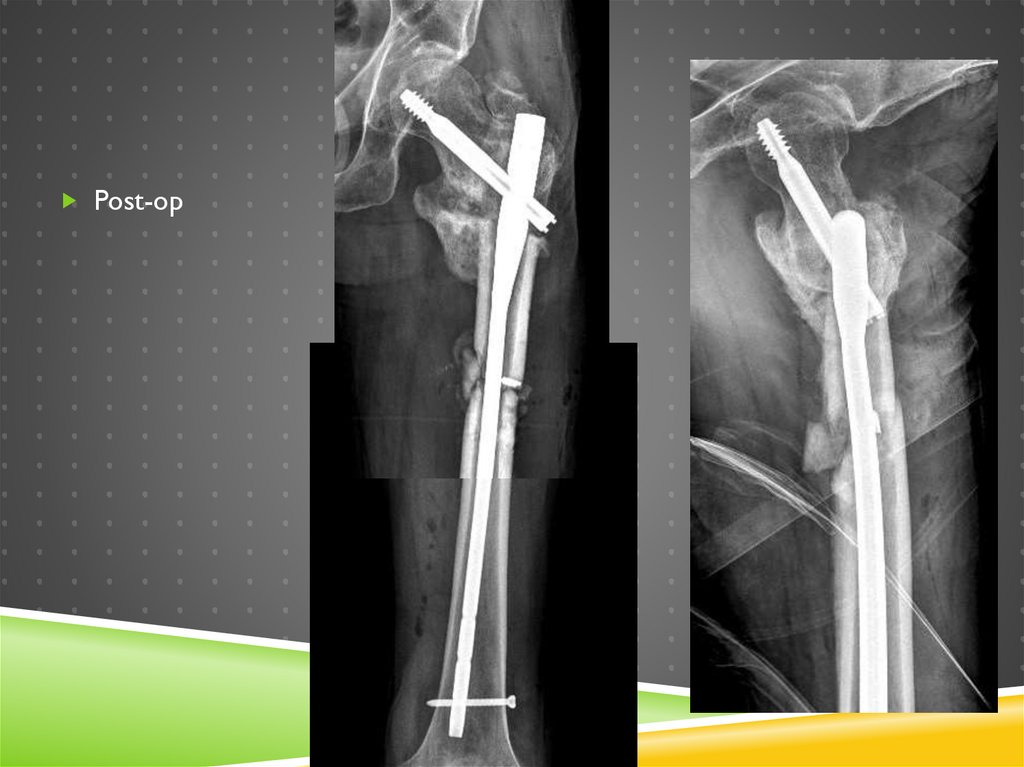

ОТЕЧЕСТВЕННАЯ КОНСТРУКЦИЯ

Post-op

Телескопирование

винта нужно?

Правильно, не нужно

Статическая фиксация

стопорным винтом

(скомбинированным с

end cup)

Наглухо, Карл!